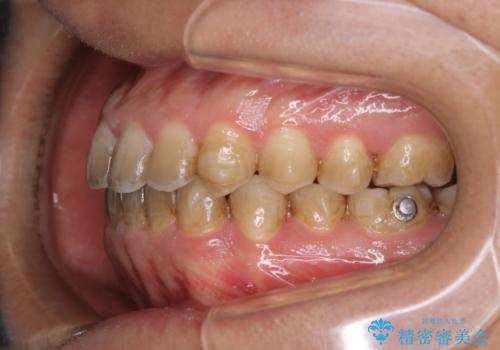

コーヒーを多く飲むインビザライン矯正中の患者様のクリーニング

60分コースでも足りないくらいの着色の量でした。

定期的にクリーニングに来られてますが、かなりの量のコーヒーを飲まれているため着色が多かったです。